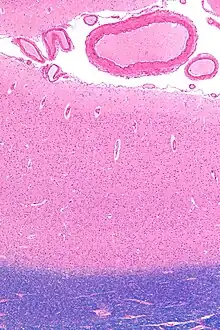

Micrograph showing the visual cortex (pink). The pia mater and arachnoid mater including blood vessels are seen at the top of the image. Subcortical white matter (blue) is seen at the bottom of the image. HE-LFB stain.